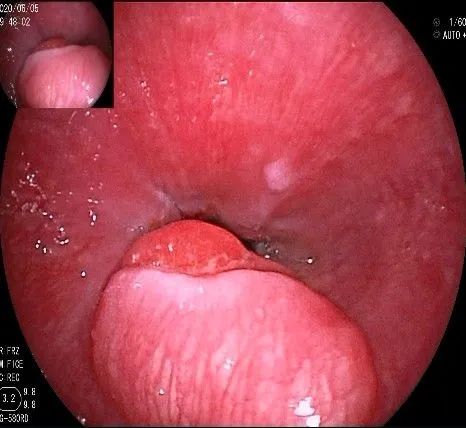

倒镜观察,可见贲门部一个明显的隆起,中央部分的凹陷,是4天前取活检留下的。

正镜观察,瘤体就在贲门部齿状线的下方。